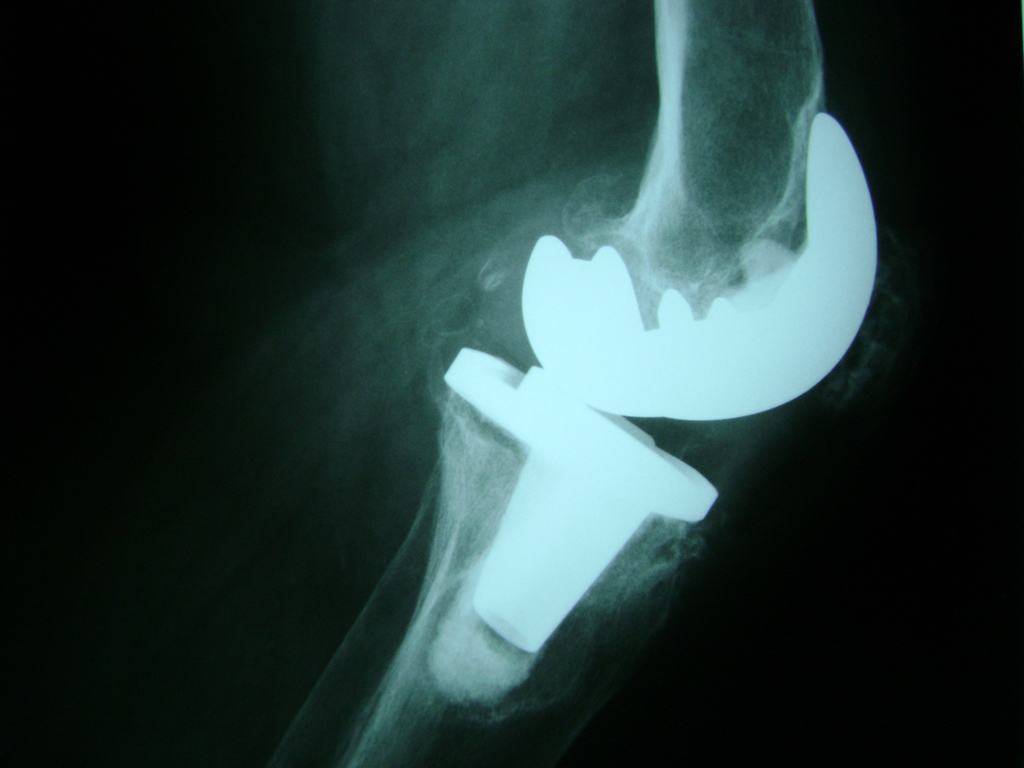

La artroscopia de rodilla es un cirugía en el cual la estructura interna de la articulación es examinada ya sea para realizar un diagnostico o para realizar un tratamiento, este procedimiento se realiza utilizando un instrumento parecido a un pequeño tubo llamado artroscopio.

La artroscopia se popularizo en 1960 y hoy en día es muy común en todo el mundo. Típicamente, es realizada por cirujanos ortopédicos de manera ambulatoria. Cuando se realiza de manera ambulatoria los pacientes pueden regresar a casa después de la operación, no se requiere quedarse en hospital.